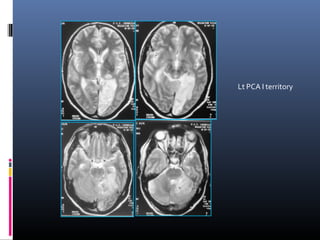

Lt PCA I territory